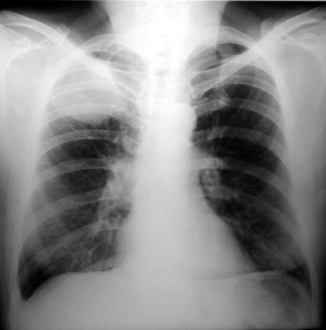

• Radiología

Radiología del tórax a su ingreso:

• Observamos lesión opaca, densidad homogénea, ubicada en el estrecho superior del tórax, pulmonar, de bordes bien definidos, redondeada, evidentemente de aspecto neoplasico.

• No se aprecian lesiones osteolíticas costales.

• Aplanamiento de los diafragmas, transparencia pulmonar bilateral, y silueta cardiaca de aspecto normal.